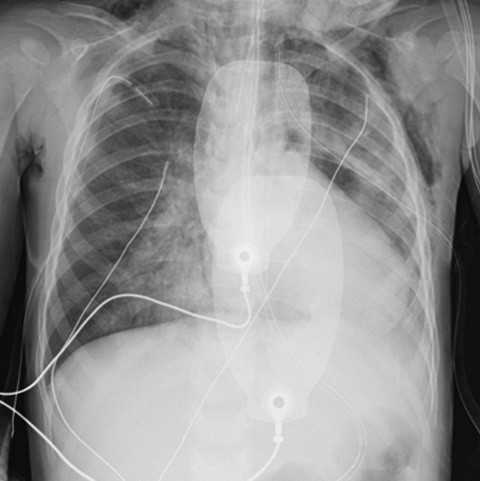

While awaiting the team's arrival, inhaled 20 ppm nitric oxide was administered (1). A new inhalation of 2.5 mg of salbutamol, along with 120 mg of intravenous theophylline and 625 mg of magnesium sulphate was also administered, but no improvement was observed in the patient. Circulatory stability was maintained with an infusion of 0.1 µg/kg/min adrenaline, but there was a life-threatening ventilation issue. It was decided to insert bilateral chest drains due to vital indications, as minimal breath sounds were heard and there were clinical and radiological signs of worsening emphysema. A subsequent chest X-ray showed increasing opacity, pneumomediastinum and emphysema (Figure 2). The antibiotic treatment was changed to a combination of 625 mg of cefotaxime and 120 mg of clindamycin intravenously.